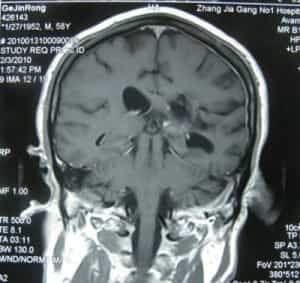

فحص بالأشعة بعد ثلاثة أشهر من الجراحة

بعد ثلاثة أشهر من خضوعه لجراحة عصبية لعلاج ورم سحائي غير نمطي، عاد المريض جينرونغ غي إلى مستشفى بي بي آي إتش للمتابعة. أفاد بأنه تعافى بشكل جيد خلال فترة مكوثه في المنزل، وأن حركة ساقيه أصبحت أكثر مرونة بكثير مما كانت عليه قبل الجراحة، وشعر بقوة ساقيه من جديد، وأن مشيته أصبحت طبيعية دون أي ضعف في ساقه اليمنى. وقد تلقى جراحة عصبية ناجحة لعلاج ورمه السحائي غير النمطي.